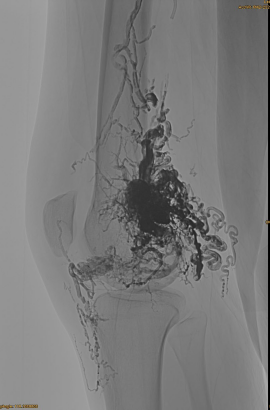

DSA initial:

Résultat final:

Presque aucune sortie veineuse:

Phase tardive, un autre EMBO nécessaire, mais beaucoup mieux: